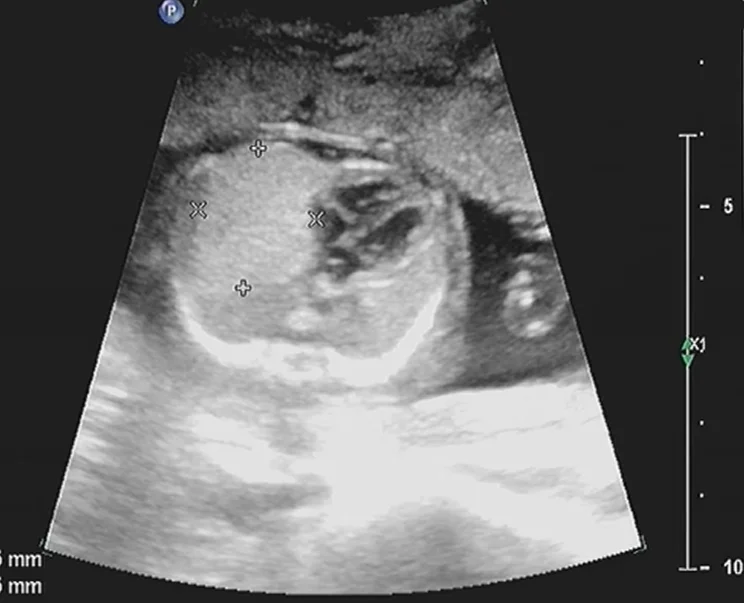

Bất thường nang tuyến phổi bẩm sinh thai nhi (Congenital Pulmonary Airway Malformation)

• Bất thường nang tuyến phổi bẩm sinh thai nhi (Congenital Pulmonary Airway Malformation)